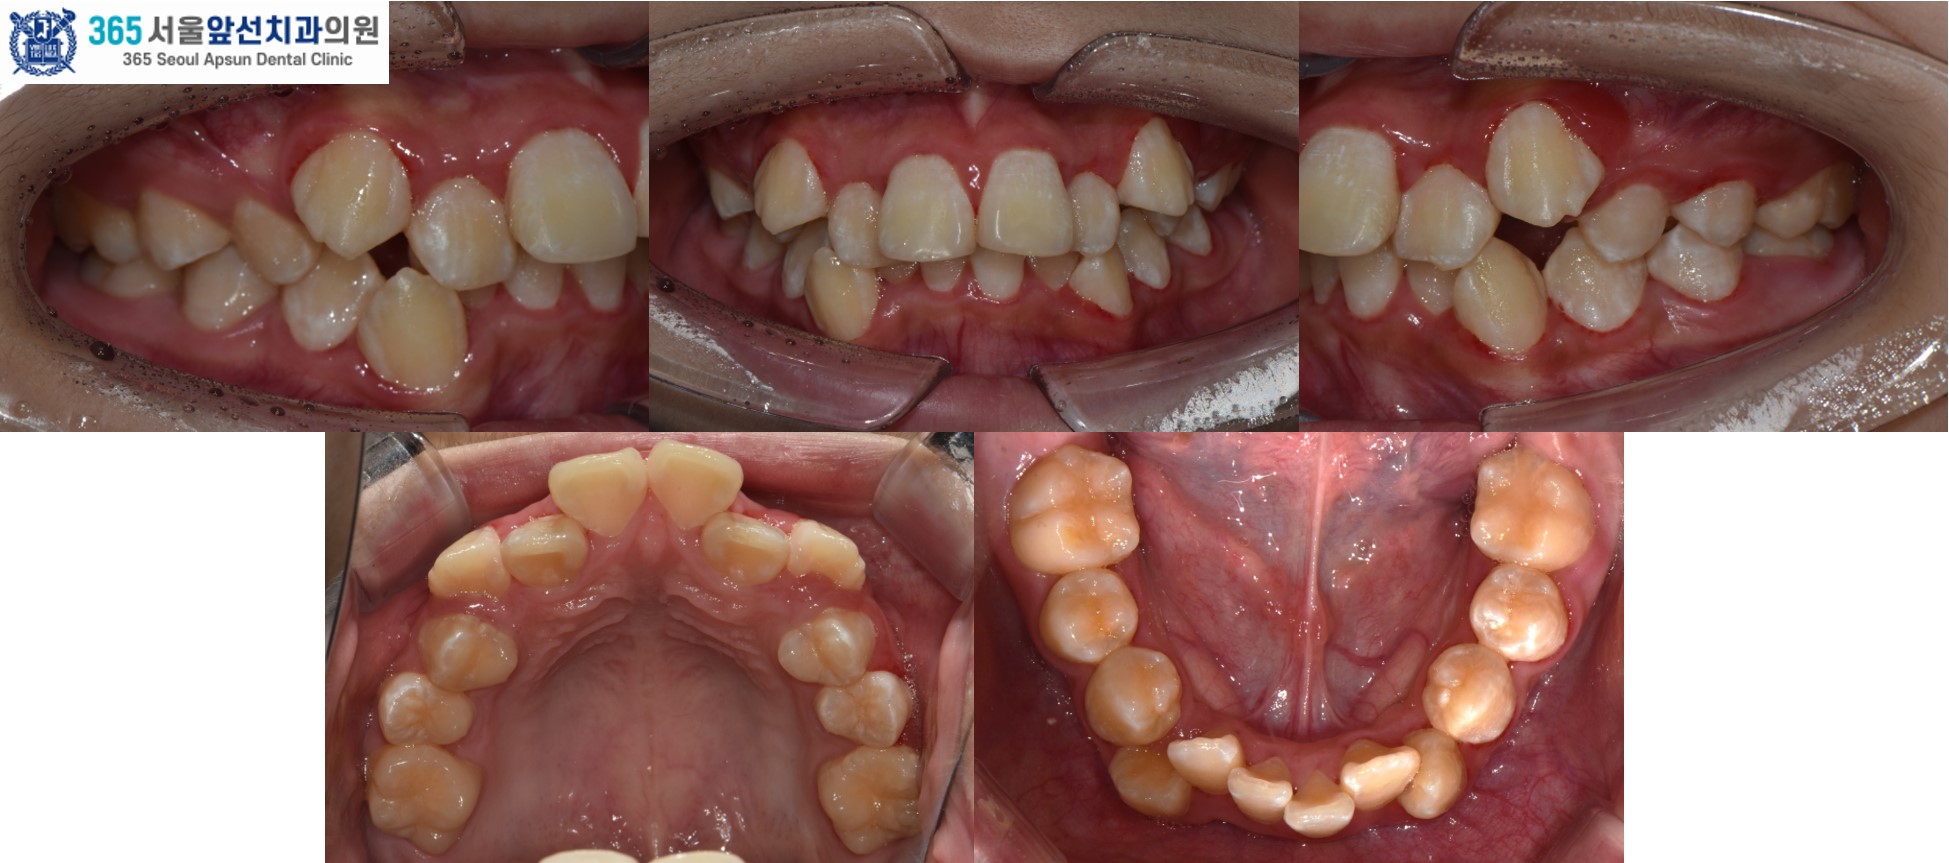

돌출입과 덧니를 고민으로 내원하신, 10대 청소년 환자 분의 증례를 소개드리겠습니다. 촬영일시 : 2024.05.21. / 2026.03.28 치료 전, 심한 공간 부족으로 송곳니 덧니와 앞니의 비뚤비뚤하게 겹친 치열이 관찰됩니다. 상악 치열의 경우 7.0mm의 공간 부족, 하악 8.5mm의 공간 부족이 있습니다. 임상적 및 방사선학적 검사 결과 위턱의 돌출과 아래턱의 후퇴를 동반한 2급 골격과, Angle씨 분류 치성 2급 부정교합 및 과도한 수직 및 수평 피개(과개교합)과 심한 총생으로 진단되었습니다. 치아 크기에 비해 악궁의 크기가 작은 부조화도 있으셔서, 비발치 교정보다는 발치 교정으로 치료하는 것이 적합합니다. 따라서, #14,24,34,44 제1소구치 치아의 발치와 전체 치열의 고정식 교정장치 치료(Clippy-C), 상악 교정용 미니임플란트를 이용한 추가적 치열의 후방이동을 계획하였습니다. 촬영일시 : 2024.05.21. 치료 후의 모습입니다. 2024년 6월 5일 치료를 개시하여 2026년 3월 28일에 교정치료를 종료하였으며 총 1년 8개월의 치료기간이 소요되었습니다. 치열이 가지런하게 배열되면서 후방이동 되어 Angle씨 분류 치성 1급 관계가 달성되었고, 얼굴형 또한 돌출입의 개선과 더불어 입술 폐쇄가 개선되었습니다.

촬영일시 : 2024.05.21. / 2026.03.28. [ 치료기간: 2024년 5월 21일 ~2026년 3월 28일 )] |